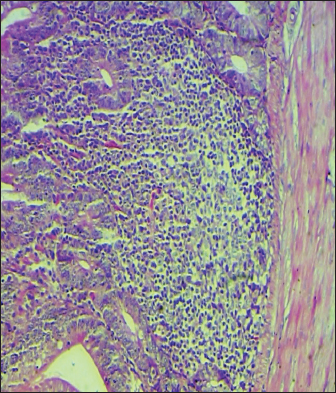

Histopathological study

The results noted in Figures 15 showed that chicks infected with S. enteritidis had edema among the muscular layer with atrophy of some intestinal villi. On the other hand, broilers infected with S. enteritidis and treated with C. myxa showed degeneration of intestinal glands with extensive inflammatory cell infiltration also mild sub-muscular edema, while with curcumin-treated group showed normal intestinal villi architectures, with hyperplasia of intestinal associated lymphoid tissue. The result noted a clear improvement in broilers that received C. myxa and curcumin showing normal intestinal villi with an increase in the number of goblet cells. The data of the present study confirmed the effectiveness of C. myxa and curcumin and especially the synergistic action between them in inhibiting the growth of S. enteritidis bacteria in poultry chickens, improving antioxidants and reducing free radicals, in addition to its action as a good anti-inflammatory at the blood level and suppressing the levels of cytokines that encourage inflammation and its role in improving intestinal tissues and making them close or similar to the health of broiler.

Fig. 2. Cross section of the intestine of chicks infected with S. enteritidis and showing edema among the muscular layer with atrophy of some intestinal villi (H & E ×100).

Fig. 3. Cross section of the intestine of poultry infected with S. enteritidis and treated with C. myxa, showing degeneration of intestinal glands with some inflammatory cell infiltration also mild sub-muscular edema (200×, H & E).